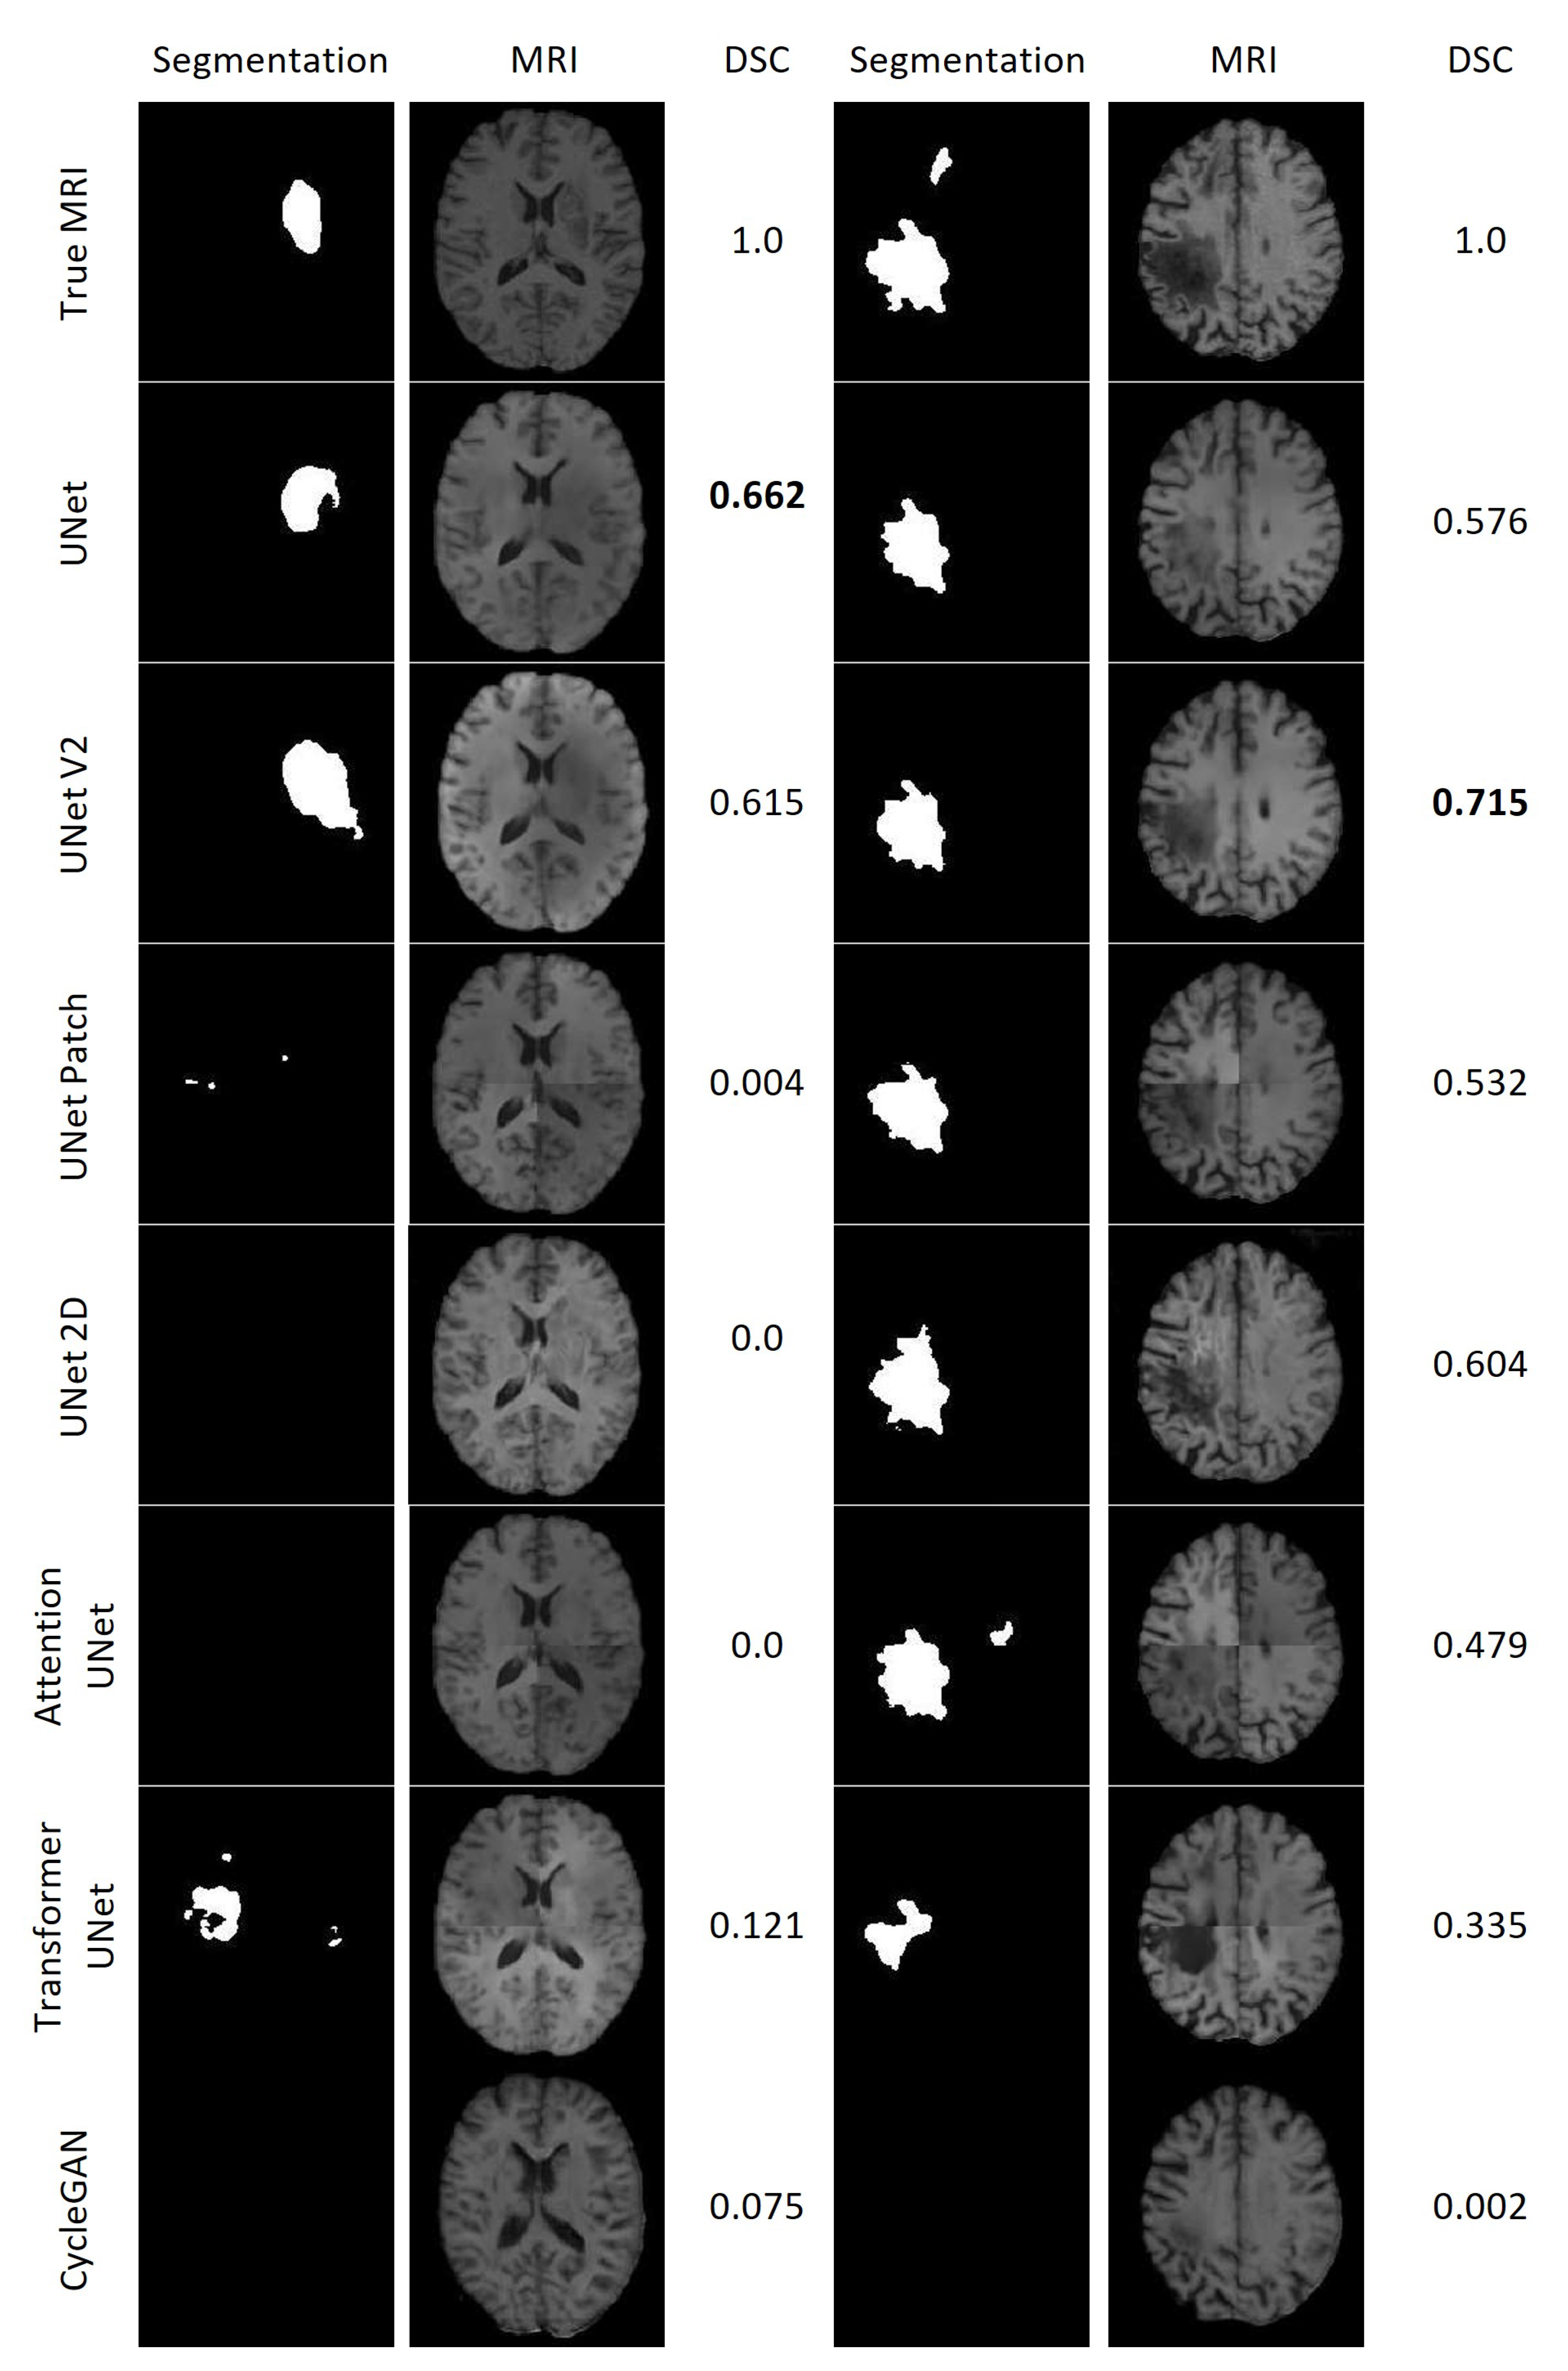

Figure 21 displays the results of the lesion segmentation algorithm applied to the synthetic and true MRIs of two patients within the test set. Patient E exhibited a smaller lesion that lacked significant contrast in any of the synthetic MRIs. Among the synthetic MRIs, only those generated by UNet and UNet V2 produced lesion segmentations resembling the original MRI for Patient E, with Dice Scores (DSC) of 0.662 and 0.615, respectively. The next best performing model was Transformer UNet, achieving a DSC of 0.121. For Patient A, all synthetic MRIs, except those generated by CycleGAN, yielded lesion segmentations resembling the true MRI. The most accurate lesion segmentation for Patient E was obtained from the UNet V2 synthetic MRI, with a DSC of 0.715.

Figure 21. Lesion segmentations of the True MRI and Synthetic MRIs for Patient E (Left) and Patient A (Right).